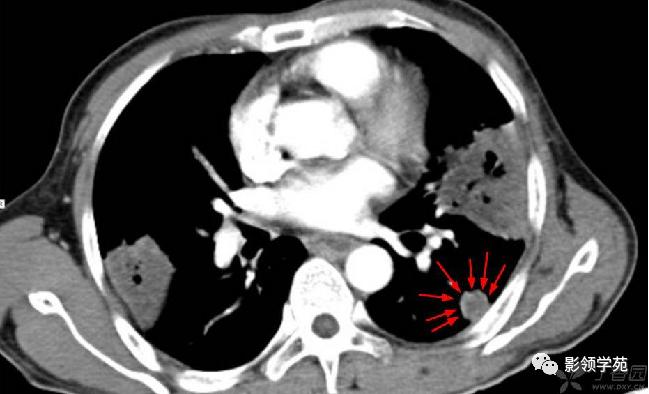

结节或肿块周围可见晕轮征、供养血管征。晕轮征提示肺结节或肿块出血,CT表现为结节或肿块周围磨玻璃密度影;供养血管征CT表现为血管影进入结节或肿块内,提示病变以血管为中心生长。

病例2:右肺下叶肿块周围见晕轮征

病例4:左肺斑片状实变,右肺中下叶结节灶,中叶结节见供养血管征。